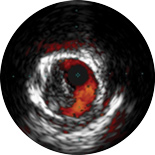

ChromaFlo provides easy assessment of stent apposition, lumen size and more by highlighting blood flow red at the touch of a button. ChromaFlo is available on Philips imaging systems.

Designed to make lumen size and stent apposition instantly recognizable and help identify branches, dissections, thrombus, and plaque distribution in bifurcations. ChromaFlo highlights blood flow red to identify:

No flushing and no special procedures are required during imaging. Simply activate ChromaFlo with a click.

ChromaFlo works with the Philips Eagle Eye Platinum digital IVUS catheters.